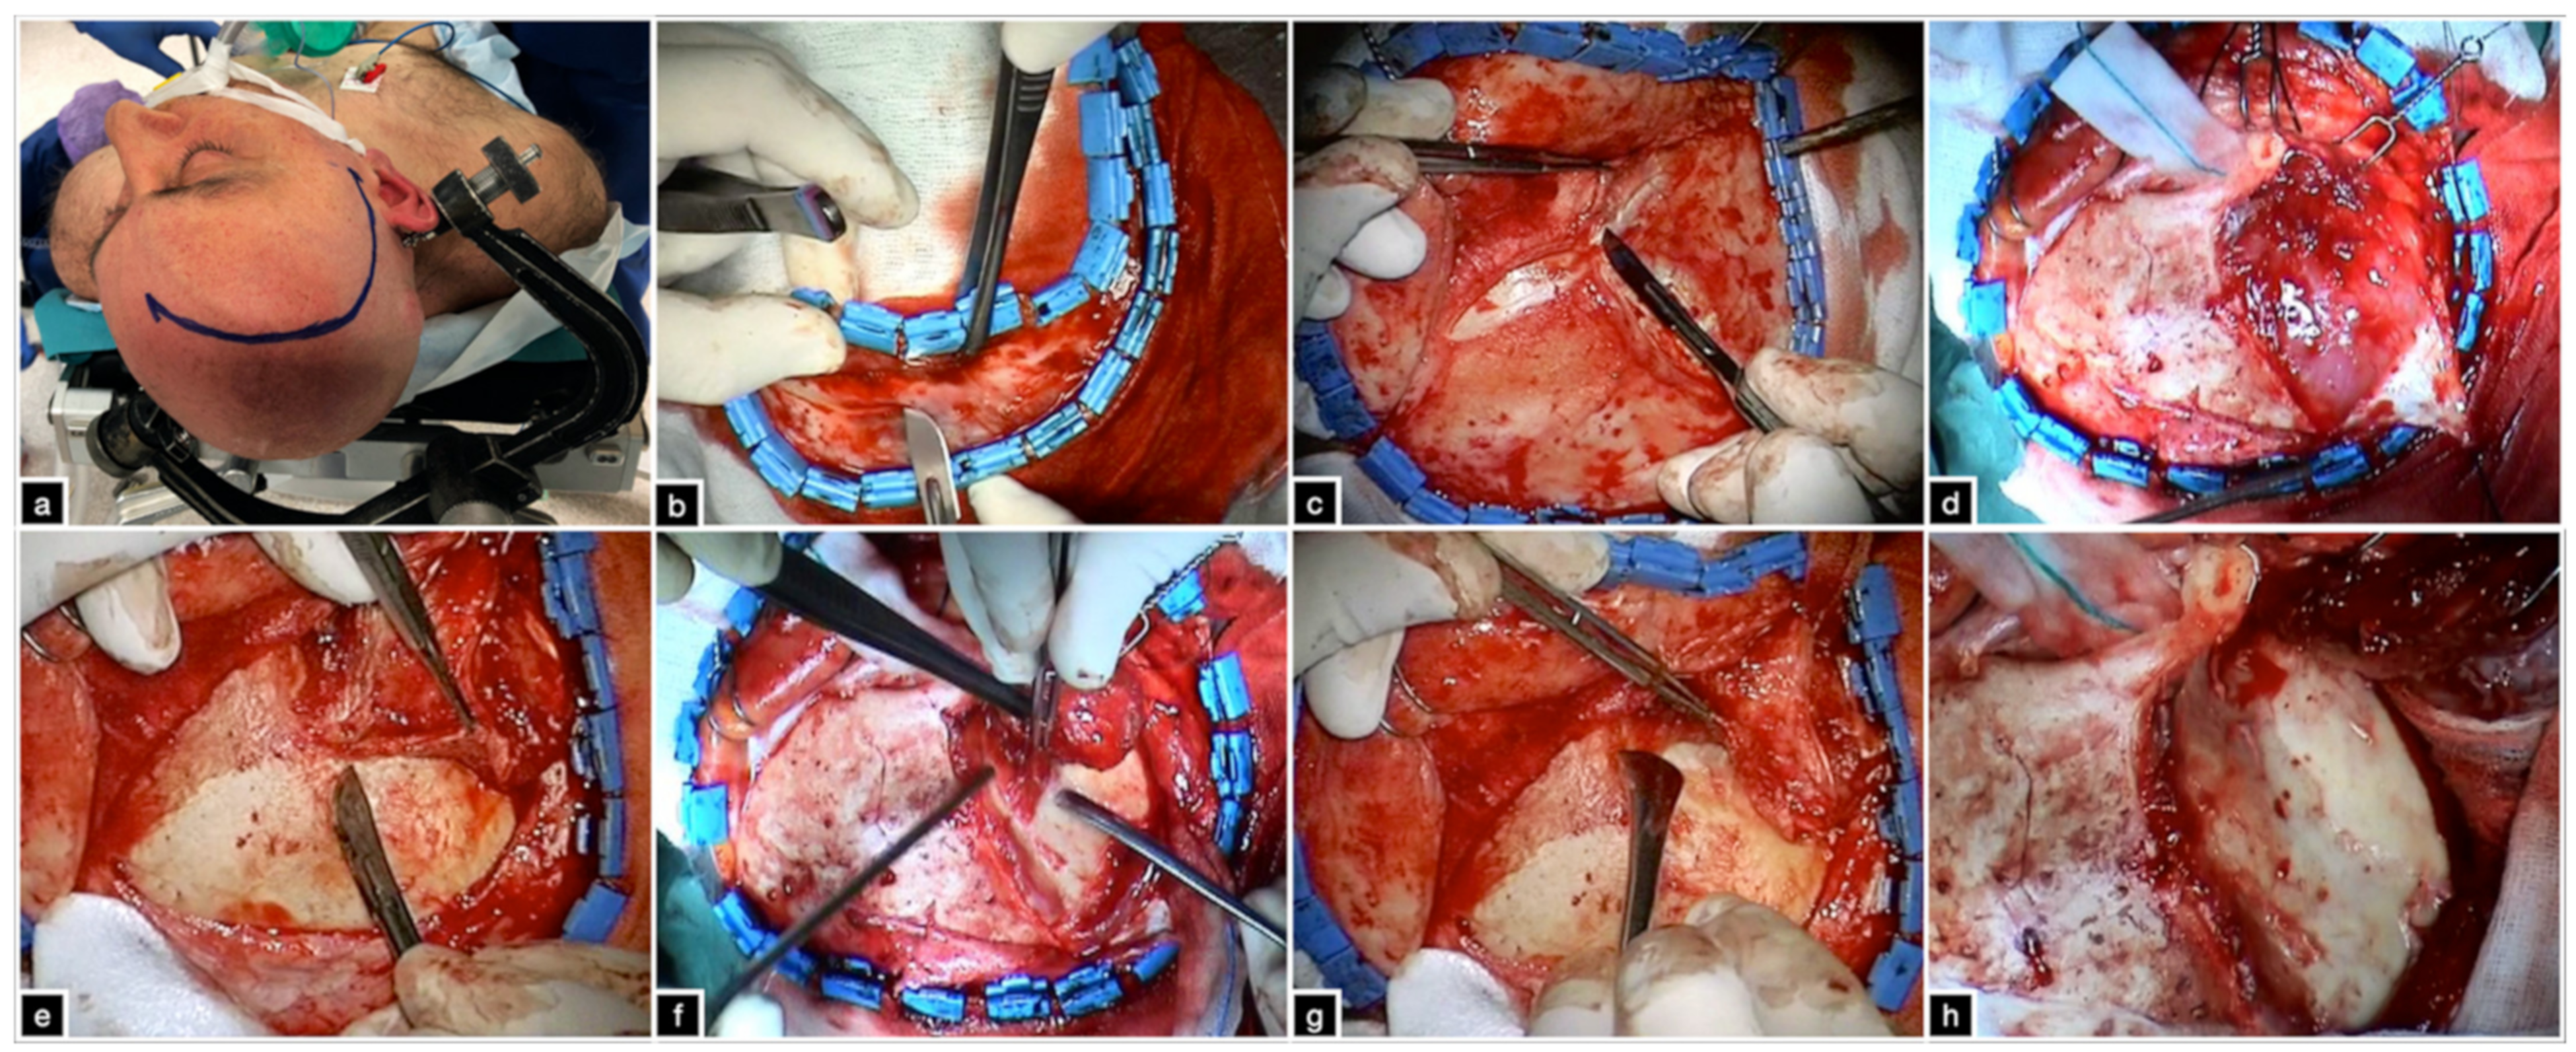

3.2.2. Skin Incision and Soft-Tissue Dissection

3.2.3. Identification of Bony Landmarks

3.2.4. Craniotomy